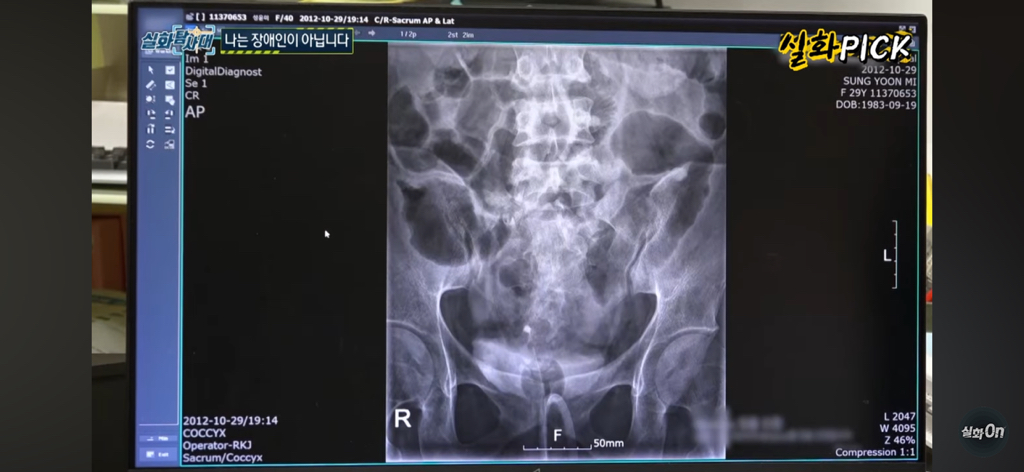

그 당시에 척추압박골절 등으로 하반신 마비가 되셨고

사고 후 12년째 휠체어를 타시고 있는데

스포츠의학 전문의를 찾아가서 보여드리니

당연히 장애등급 나올 수 있다 하심 ㅠㅜㅠ